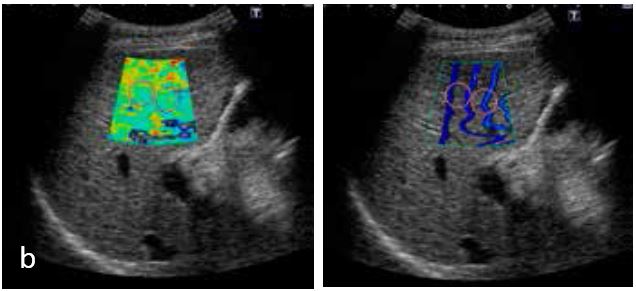

Нижче наведено випадок F1/A1 (хронічний гепатит) і випадок F4 (цироз) зі швидкістю зсувної хвилі 1,51 м/с і 3,32 м/с відповідно (рис. 10).

На основі кольорової карти колір змінюється з синього на жовтий/червоний, коли швидкість зсувної хвилі збільшується. Лінії на карті розповсюдження широко розділені в F4. Обидва випадки демонструють рівномірне поширення зсувних хвиль. Великі структури, такі як кровоносні судини на карту не потрапляють.

Середнє значення: 1,51 м/с. F1, A1 (хронічний гепатит)

Середнє значення: 3,32 м/с. F4 (цироз)

Рисунок 10. (а) Випадок хронічного гепатиту та випадок (б) цирозу печінки